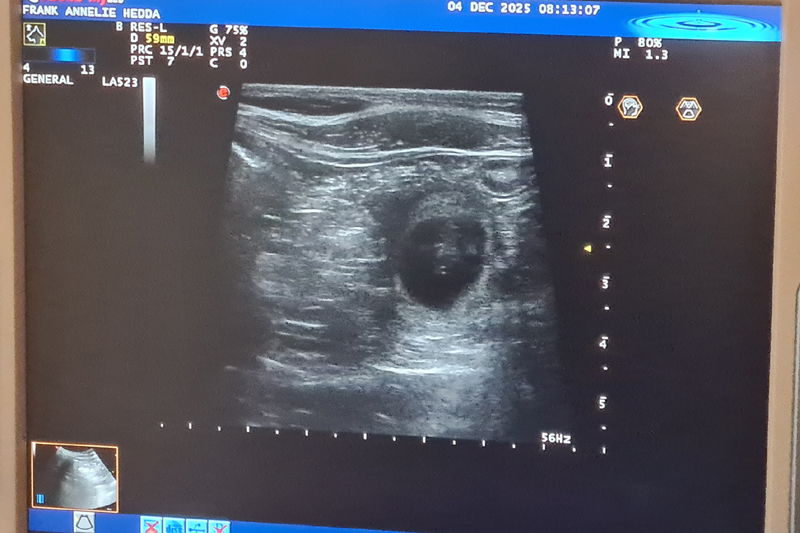

Lotta är dräktig!!

Vi har gjort ultraljud och det finns många valpar i Lottas mage!! Stolt pappa är Bertil (Actualis Winter Surprise).

Valparna föds i mitten av januari och vill flytta till sina nya familjer i matten av mars.